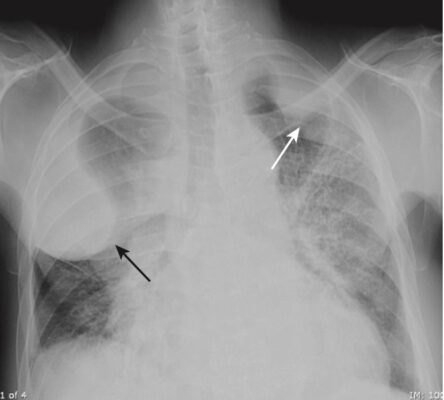

- Hội chứng Dressler (Box 1, Hình 1)

| Box 1 HỘI CHỨNG DRESSLER |

| Còn được gọi là hội chứng sau phẫu thuật cắt màng tim / sau nhồi máu cơ tim. Thường xảy ra từ 2 đến 3 tuần sau nhồi máu cơ tim xuyên thành, gây tràn dịch màng phổi trái, tràn dịch màng ngoài tim và bệnh vùng khoảng chứa khí từng đám ở đáy phổi trái. Kèm với đau ngực và sốt, nó thường đáp ứng với aspirin hoặc steroid liều cao. |